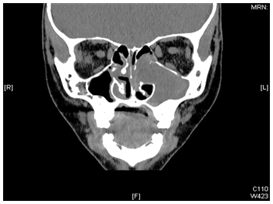

Figure 2 Axial CT scan showing large, inhomogeneously enhancing mass in the left maxillary sinus and nasal cavity. The nasal turbinates and the medial wall of maxillary sinus had been eroded by the mass.